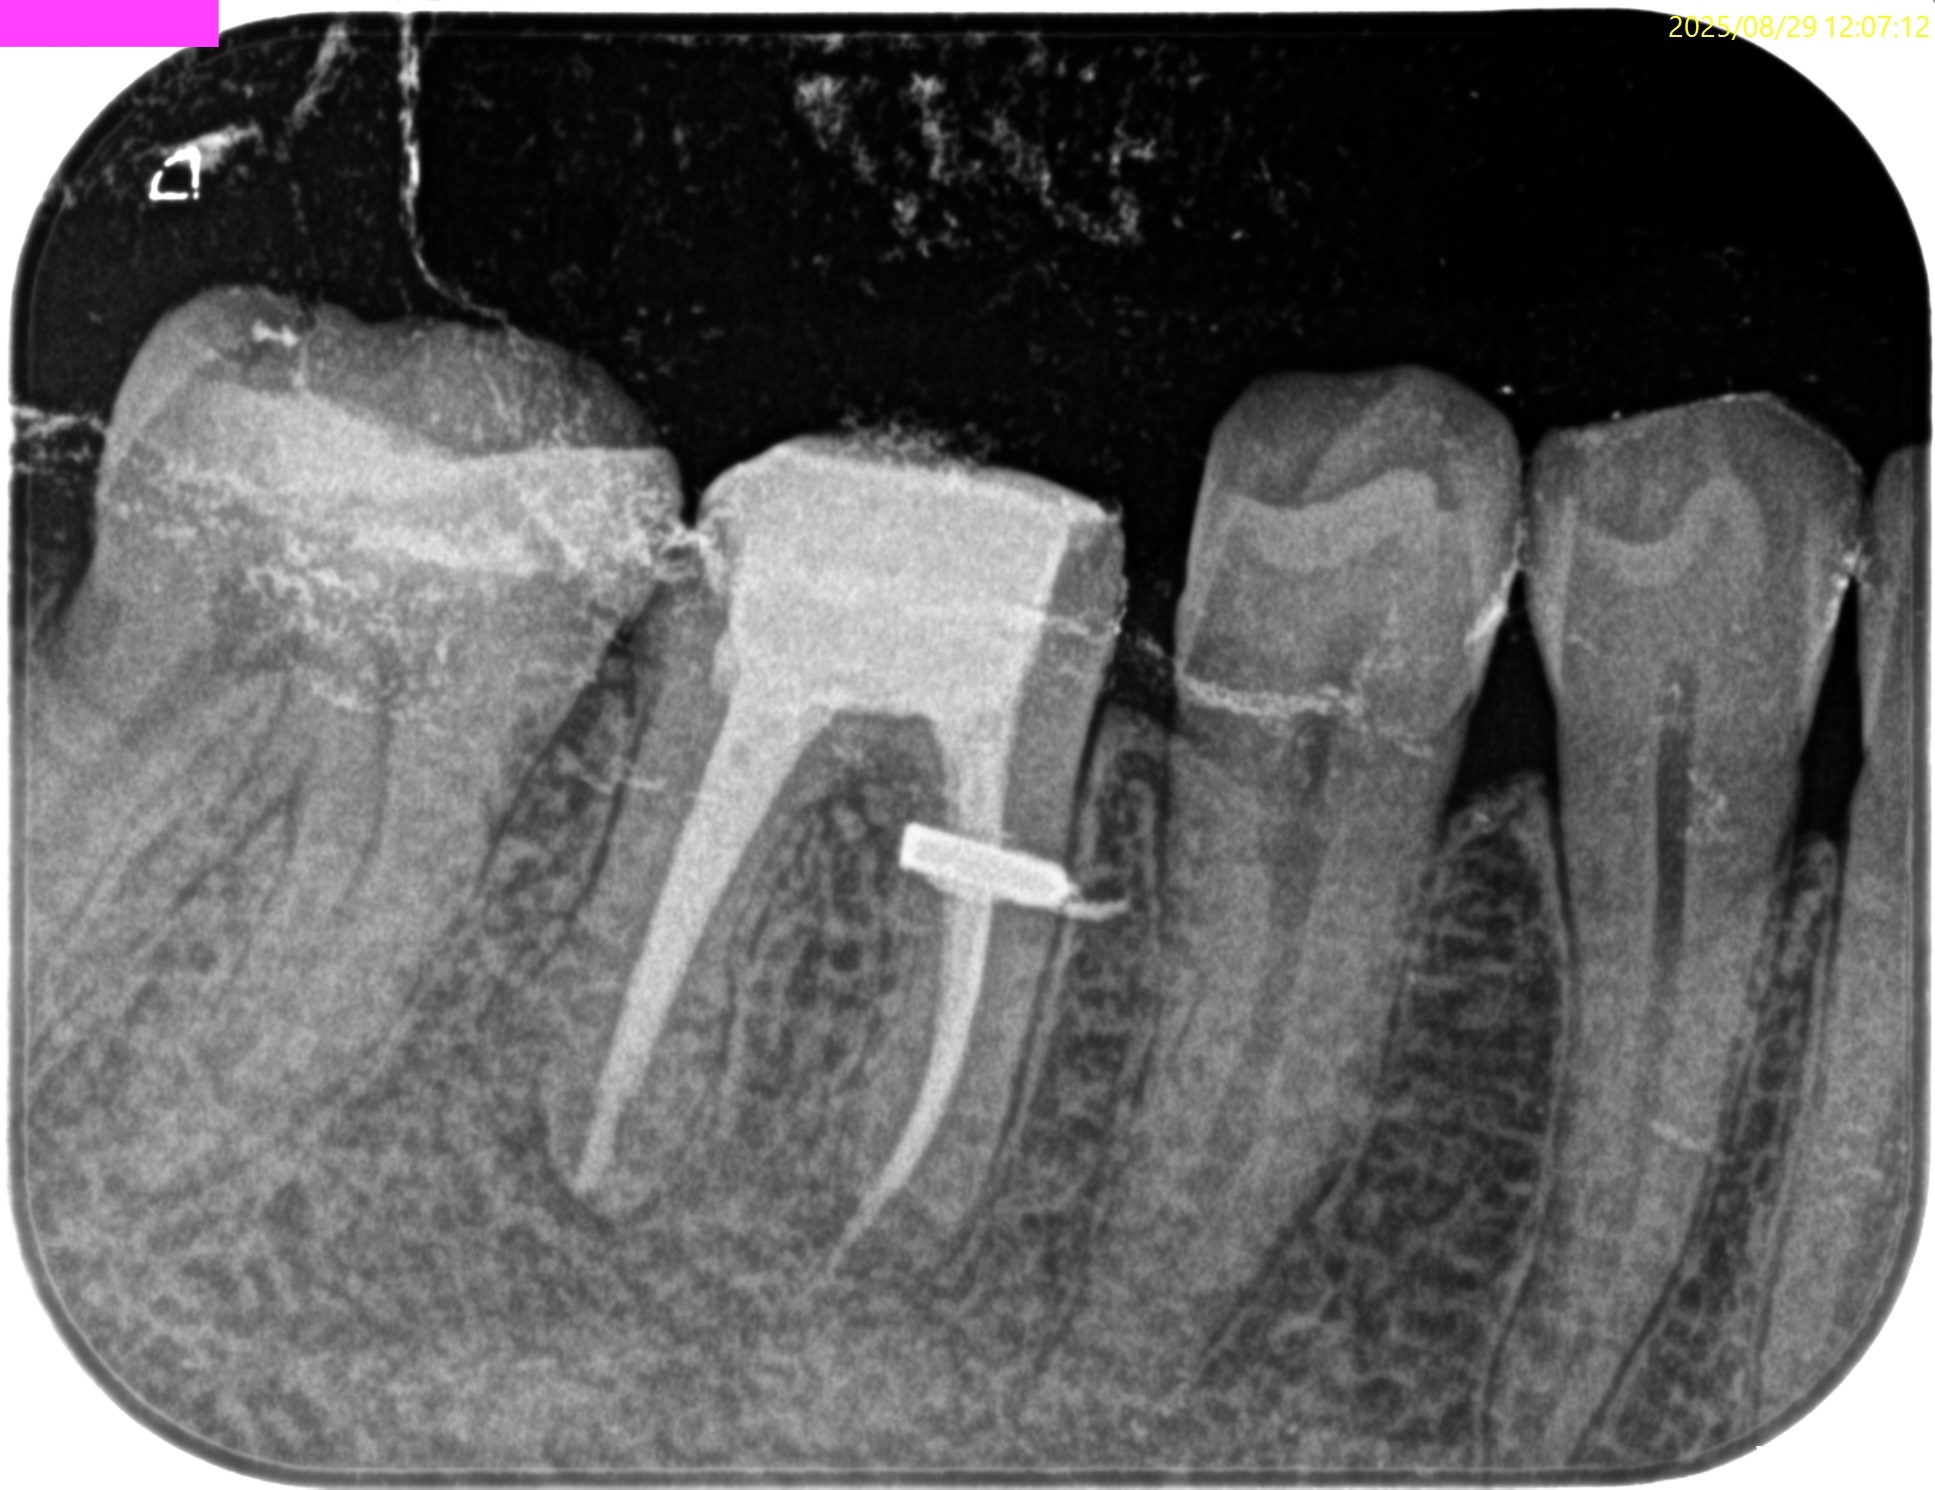

#30 Re-RCT(2025.8.29)

まず既製ピンを除去する。

その方法は動画を参考にされたい。

その後、Gutta Percha Pointの大部分を超音波で、またレジンコアを短針で突いて除去した。

根尖部にGutta Percha Pointが残っているじゃないか!と言うあなた。

それを完全に除去することは文献上、不可能なのですよ。

この後、C-solutionと併用して作業長を測定した。

まずDからである。

K 25で穿通した。

ということは…HyFlex EDM #25は使用できないであろう可能性が高い。

次にMLにファイルを挿入するが穿通しなかった。

MBにファイルを挿入する。

この際、Gutta Percha Pointを除去するファイルも超音波とともに使用している。

MBはK#20で穿通した。

以下のように形成・根充している。

術後にPA, CBCTを撮影した。

MB

ML

D